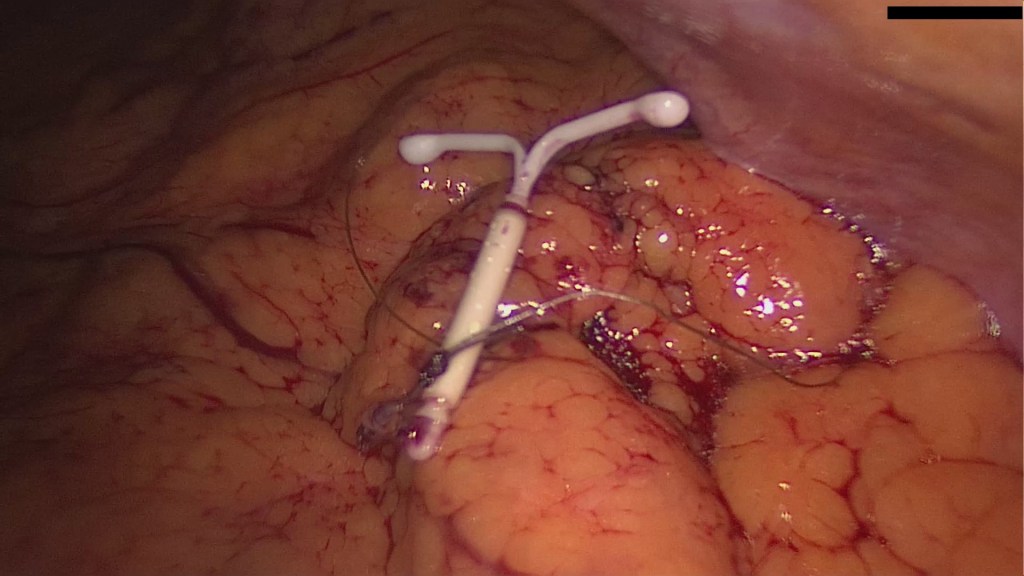

The patient insisted for more examinations, since she was not convinced that the old IUD simply disappeared. This led eventually to an x-ray of the abdomen which clearly showed two IUDs; one intrauterine and one intraabdominal.

The patient came to us for removal. In our work-up we asked for a preoperative low-dose abdomen CT, which verified intraperitoneal lie of the IUD and excluded bowel involvement.

Interestingly, the patient had experienced the desired amenorrhea for almost 5 years, despite the fact that the IUD was lying inside the greater omentum and not inside the uterus.